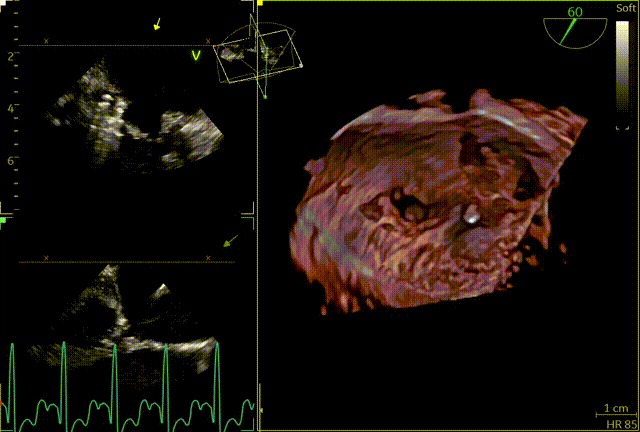

3D

3D辅助辅助观察点位

穿刺高度

3D复测穿刺高度